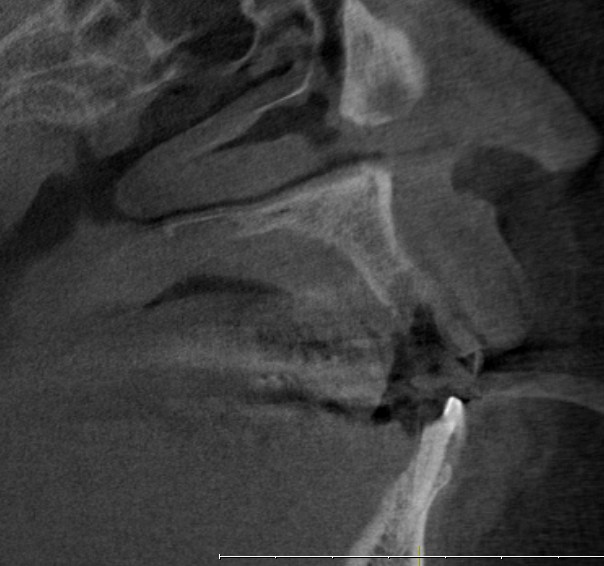

Bei nicht oder nicht vollständig durchgebrochenen Weisheitszähnen wird die darüber liegende Schleimhaut beiseite geschoben und der darüber liegende Knochen entfernt. Dann wird der Zahn mit einem Hebel entfernt. Ist dies aus anatomischen Gründen nicht im Ganzen möglich, wird das Durchtrennen des Zahnes notwendig. Das Trennen des Zahns ist obligat wenn die Platzverhältnisse keine andere Entfernungsmethode zulassen oder sich die Zahnwurzeln in unmittelbarer Nervnähe befinden. Die Wunde kann vernäht oder offen gelassen werden. Um Folgeschäden wie eine Taubheit der Unterlippe zu vermeiden kann präoperativ ein 3D DVT ( DIGITALES VOLUMENTOMOGRAMM ) zur Abklärung der Lagebeziehung von Wurzeln und Nerv sowie zur OP-Planung angefertigt werden.

Zu einer Wurzelspitzen-Entfernung wird Ihr Zahnarzt oder Kieferchirurg dann raten, wenn ein chronisch entzündlicher Prozess durch eine Wurzelbehandlung nicht behoben werden kann oder eine konventionelle Wurzelbehandlung nicht möglich ist. Auch wenn sich im Röntgenbild Veränderungen im Bereich der Wurzelspitze zeigen, die nicht eindeutig zuzuordnen sind, kann eine Wurzelspitzen-Resektion empfehlenswert sein. Um die Region der Wurzelspitzen genauer abzubilden ist es präoperativ möglich, durch ein 3D DVT (DIGITALES VOLUMENTOMOGRAMM) die Region dreidimensional abzubilden, um so eine bessere OP-Planung zu erhalten oder sich über die Frage der Erhaltungswürdigkeit des Zahns klar zu werden.

Solch ein Vorgehen erfordert allerdings auch eine möglichst exakte Diagnostik, die bei uns in der Regel dreidimensional mittels DVT erfolgt. So kann die Implantation vorher am Rechner dreidimensional simuliert werden, bevor sie am Patienten durchgeführt wird.